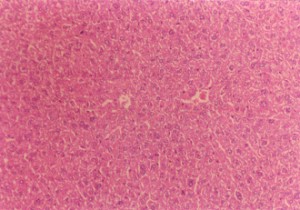

健全なマウスの肝臓(200×)